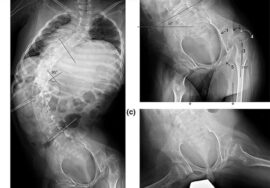

في حال ملاحظة أي من هذه العلامات، يجب استشارة الطبيب على الفور لعمل فحص سريري وتصوير بالأشعة إذا لزم الأمر.

متى يحتاج الطفل المصاب باعوجاج العمود الفقري إلى علاج؟

إذا كان الانحناء بسيطًا، قد يكتفي الطبيب بالمتابعة الدورية.

إذا كان الانحناء متوسطًا، قد يوصى باستخدام الحزام الطبي PioBrace الذي يساعد في تصحيح الانحناء ومنع تطوره.

في الحالات الشديدة التي لا تستجيب للعلاج غير الجراحي، قد يتم اللجوء إلى الجراحة.

الاعوجاج حالة مستمرة ولهذا السب قد تحتاج تدخلًا في مراحل مختلفة من العمر. وبفضل وجود تقنيات التصنيف المعتمدة ، يمكن للأطباء تصميم خطة علاجية مخصصة تضمن تدخلاً جراحيًا عند الضرورة أو العلاج غير الجراحي قبل ذلك، لتفادي الاضطراب في الوظائف التنفسية أو أي أعراض متأخرة. فريقنا المحترف يضم نخبة من الأطباء والمتخصصين الذين يجمعون بين الخبرة والاحترافية لتقديم خطة علاجية شاملة ومخصصة لحالتك، تضمن السيطرة على الانحناء ومنع زيادته.